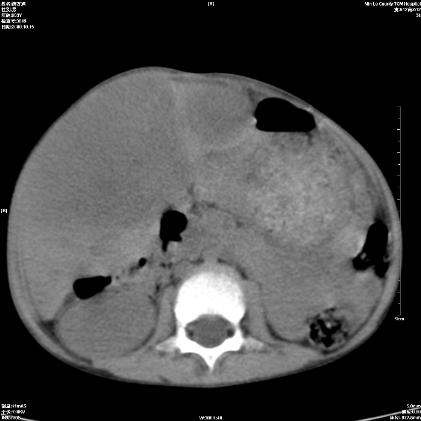

标题: PED1609:男性,3岁。彩超示肝Ca.

3岁;肝低密度灶;有钙化;有转移灶;考虑肝母细胞瘤;查afp

考虑神经母细胞瘤并肝转移